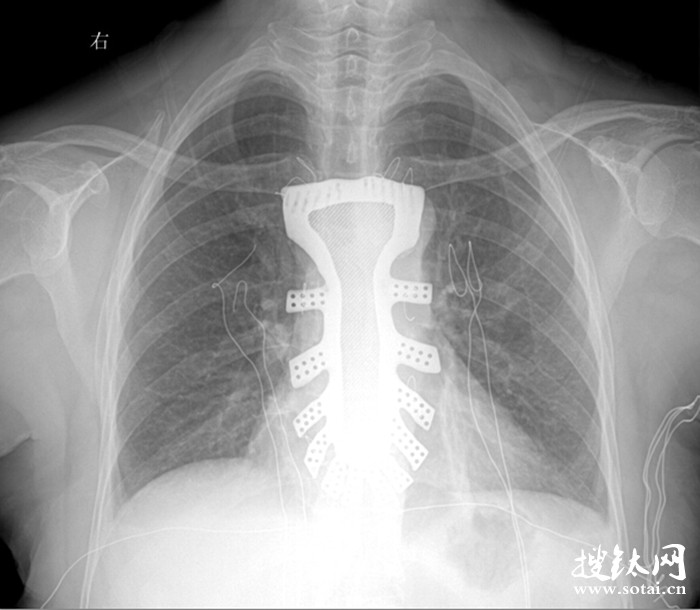

據王小平教授介紹,唐都醫院3D打印小組經過精密計算患者胸骨的大小、形狀等,充分研究討論,歷時一周,為患者設計出了手術使用的3D胸骨模型,并與西北工業大學凝固技術國家重點實驗室合作,為患者打印出了1:1鈦合金胸骨模型。隨后,又對該模型進行了一系列嚴密的醫學處理。

“手術歷時2.5小時,對患者的胸骨進行了整體切除,置換了鈦合金胸骨,目前患者恢復良好,未發現任何并發癥。”王小平教授稱,根據專業機構檢索,該手術是世界首例針對胸骨腫瘤疾病,將3D打印的可植入性鈦合金胸骨植入人體,實現病變胸骨的整體置換的手術。該手術的成功意味著未來將會為更多的胸骨腫瘤患者帶來福音。